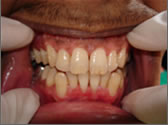

Early symptoms of gum disease include gum bleeding without pain. Pain is a symptom of more advanced gum disease as the loss of bone around the teeth leads to the formation of gum pockets. Bacteria in these pockets cause gum infection, swelling, pain, and further bone destruction. Advanced gum disease can cause loss of otherwise healthy teeth.

It is a progressive inflammatory disease of the gums and the surrounding tissue around the teeth. It is commonly known as gum disease and was referred to as pyorrhea in the old days. It is estimated that up to 80% of the population above the age of 40 may suffer from this disease with the severity varying drastically from one person to another. Periodontitis is the number one cause of tooth loss after the age of 40.

If you notice any of the following signs of gum disease, schedule an appointment immediately:

Fig. 2 |